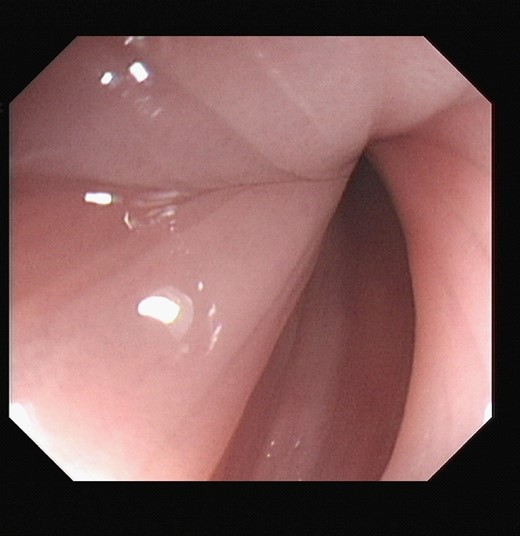

At sigmoidoscopy, the volvulus was successfully decompressed. The mucosal lining was pink and healthy in appearance, Fig. 4. Mr. X improved following this intervention.